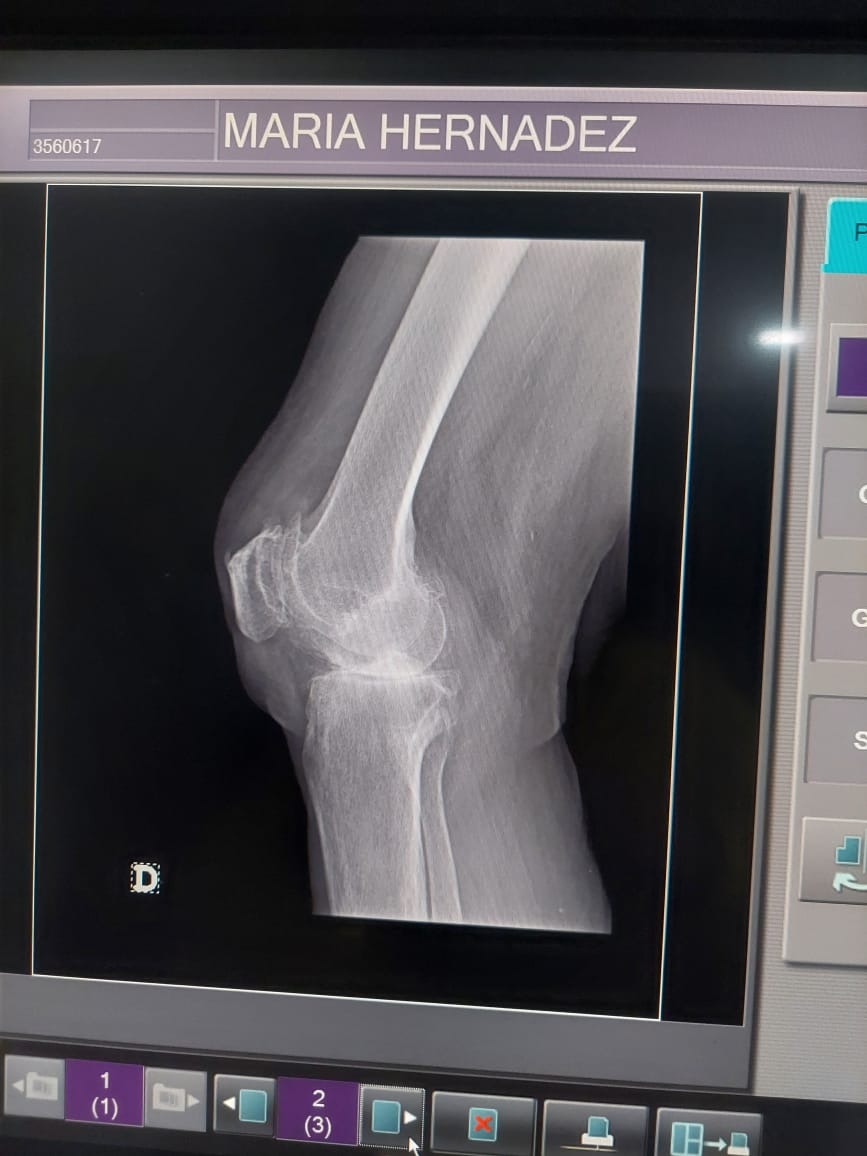

My mom has been diagnosed with severe osteoarthritis in her right knee, a condition that causes her constant and debilitating pain. After being evaluated by two medical specialists, both agreed that the only viable solution is a total knee replacement.

Mi mamá ha sido diagnosticada con artrosis severa en la rodilla derecha, una condición que le ha causado un dolor constante y limitante en su vida diaria. Después de ser evaluada por dos médicos especialistas, ambos coincidieron en que la única solución viable es una prótesis total de la rodilla derecha.